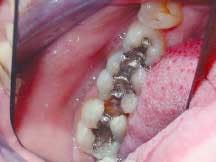

The patient presented with the mesial marginal ridge of Tooth No. 31 fractured, and the distal marginal ridge of Tooth No. 30 fractured. Secondary decay was present around the tarnished and worn amalgams in Teeth Nos. 29 through 31 (Figure 1). Following the placement of a rubber dam, the amalgam restorations and carious tissues were removed. The teeth were then prepared to proper cavity form for the placement of ceramic onlays. Next, the teeth were powdered with an optical contrasting agent (Vita) (Figure 2). A series of optical impression images were taken to record the entire lower right quadrant in the same impression (Figure 3).